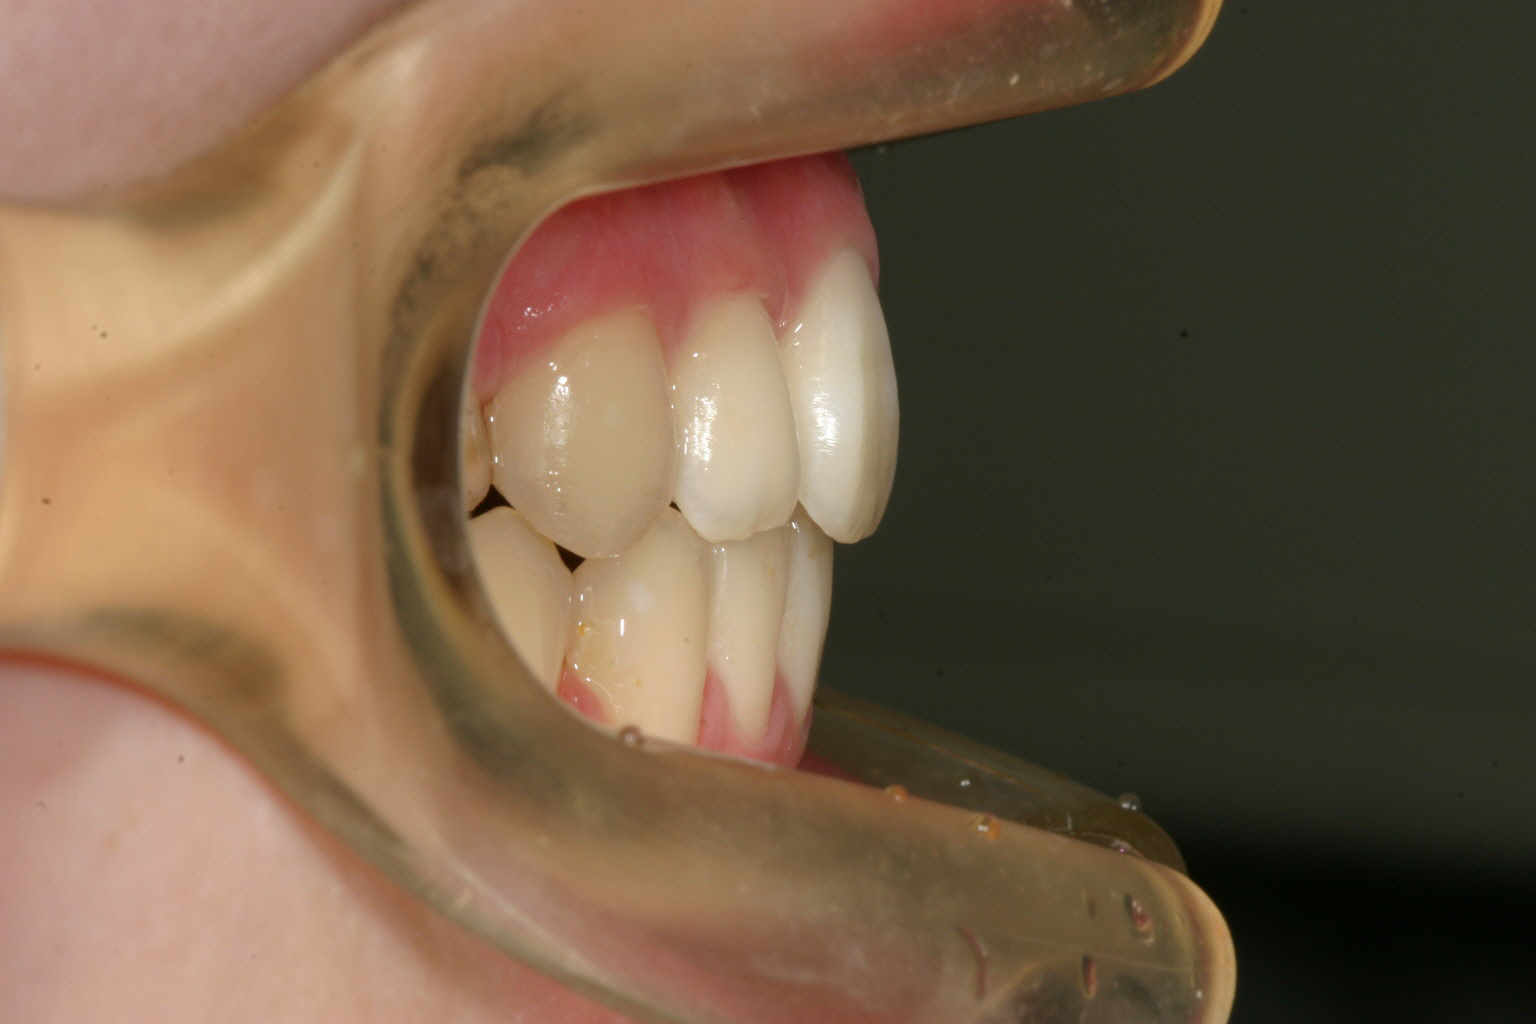

横から見ますとオーバージェットも大きいです。

両サイドの小臼歯抜歯して前歯の出っ張りを中に入れました。

下顎は非抜歯です。アーチをU字に変えて綺麗に並んでます。